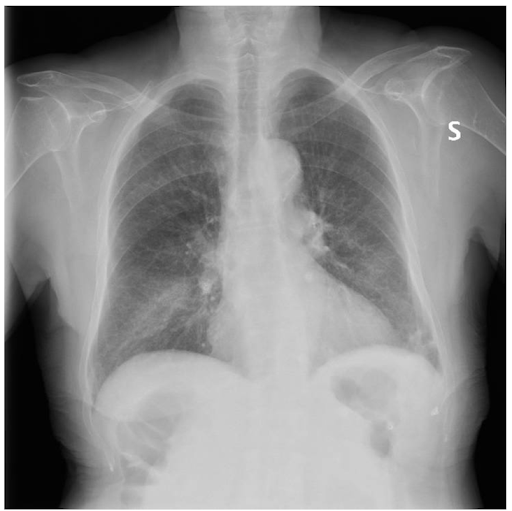

Es wird eine Röntgenaufnahme des Brustkorbs angefertigt. Das Bild zeigt eine interstitielle Verdickung auf bibasaler Höhe, in deren Zusammenhang eine unscharfe Verdickung an der Basis der rechten Lunge zu erkennen ist.